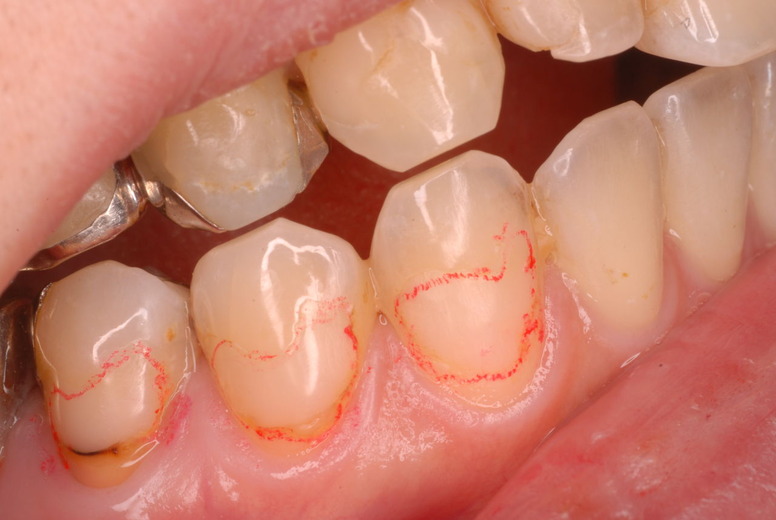

親知らずを取ることを嫌がる方が多いのですが、もし親知らずとその隣の14歳大臼歯の間に虫歯ができたり歯周病を罹患した場合、どれほど治療が大変で再発も起こりやすいか理解できない方がおおいのです。

写真左下の親知らずが痛くなり抜歯しました。その後歯茎を除去して虫歯を露出させる処置を二回ほどしています。

レントゲンでは小さいですが、こう言う虫歯が一番怖いのです。

治療の成功率は極めて悪くすぐ再発しやすいのです。